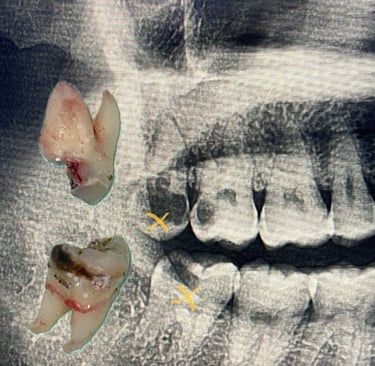

Minor Oral Surgery (MOS) is a routine dental procedure used to treat conditions such as impacted wisdom teeth, broken tooth roots, or oral infections that require more than standard dental care.

At Lau Dental Clinic & Surgery, we are fully equipped with on-site X-ray facilities, allowing us to assess and diagnose your condition quickly and accurately — often enabling same-day treatment. With extensive experience in managing a wide range of MOS cases, our highly skilled dental surgeon can perform most procedures safely and efficiently during your visit.

Minor Oral Surgery involves small surgical procedures done inside the mouth, often under local anaesthesia. The most common reason patients need MOS is to remove impacted or partially erupted wisdom teeth. However, it’s also used for removing broken tooth roots, treating dental cysts, or even preparing the mouth for dentures or implants. Unlike major surgery, MOS is minimally invasive, doesn’t require general anaesthesia, and is usually completed in under two hours.

At Lau Dental Clinic & Surgery, the process begins with a thorough consultation and digital X-ray, all done in-house. This allows us to assess your condition on the spot — and in many cases, proceed with treatment on the same day.

Once you're comfortable and the area is numb, our experienced dentist gently makes a small incision to access the tooth or problem area. Depending on the complexity, the tooth may be removed whole or in smaller sections. The site is then cleaned and stitched if necessary. Most MOS procedures here take only about 1 to 1.5 hours, and patients are often surprised by how quick and painless it feels.